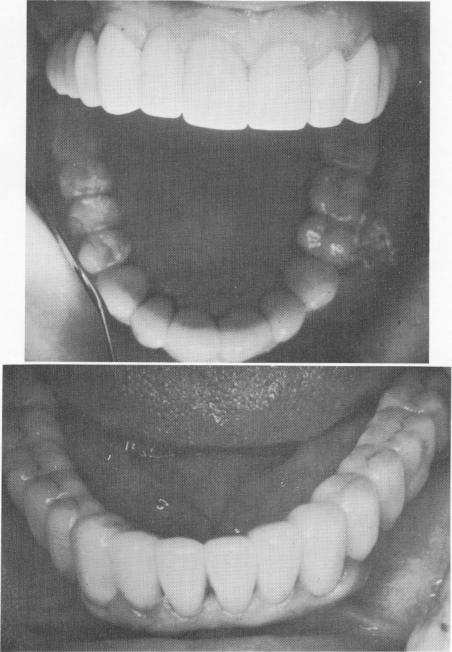

Less than 1 week later the tissue around the implants was almost entirely healed (Fig. 11-64). Both upper and lower porcelain-fused-to-metal full arch dentures were temporarily inserted so that the patient could test them for pain resulting from pontic impingements on the soft tissues. This is very important, since sometimes the pain experienced from impingement is far worse than any pain produced by a faulty implant.

Fig. 11-64. The implant site 5 days later. Considerable healing has taken place.